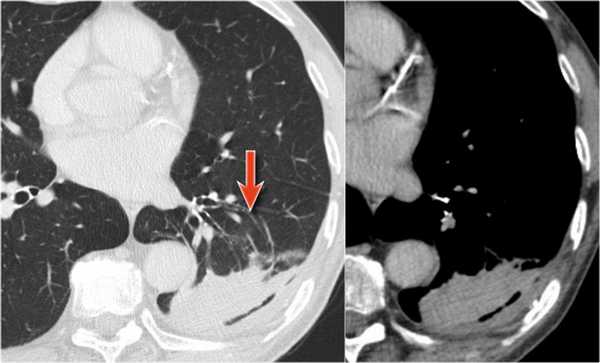

На КТ снимках синей стрелкой указан долевой ателектаз, а красной стрелкой опухоль, которая обтурирует левый верхний долевой бронх (центральный рак легкого.

Ателектаз верхней доли левого легкого с типичным симптомом воздушного серпа (Luftsichel sign — luft(air)+sichel(sickle)), обусловленный гипервентиляцией верхнего сегмента нижней доли левого легкого на фоне коллапса верхний доли левого легкого. Гипервентилируемый